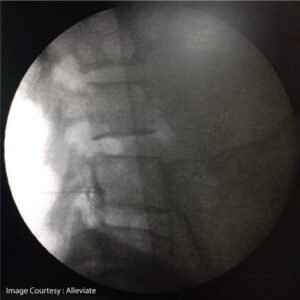

Fluroscopy Guided Transforaminal Epidural Injection